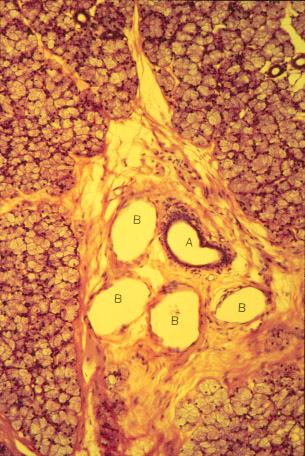

K-slide 58: High magnification of slide 55

A. Interlobular duct

B. Blood vessels